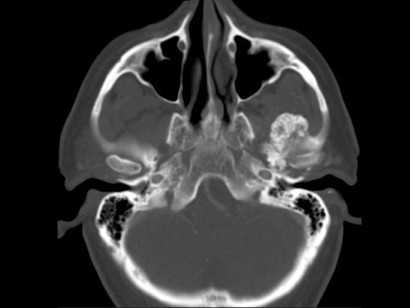

男,60岁,张口受限半年,CT检查如图所示,正确的描述或诊断是()

A.左侧颞颌关节周围软组织内见较多致密钙化影

B.左侧颞颌关节软组织未见肿胀

C.左侧颞颌关节面(颞骨面)骨质增生明显

D.左侧颞颌关节滑膜骨软骨瘤病

E.颞颌关节功能紊乱